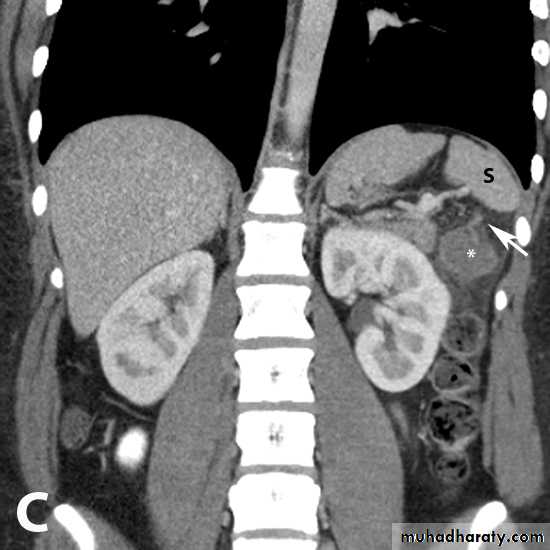

Left sided RENAL CELL CA large heterogeneous necrotic mass lesion